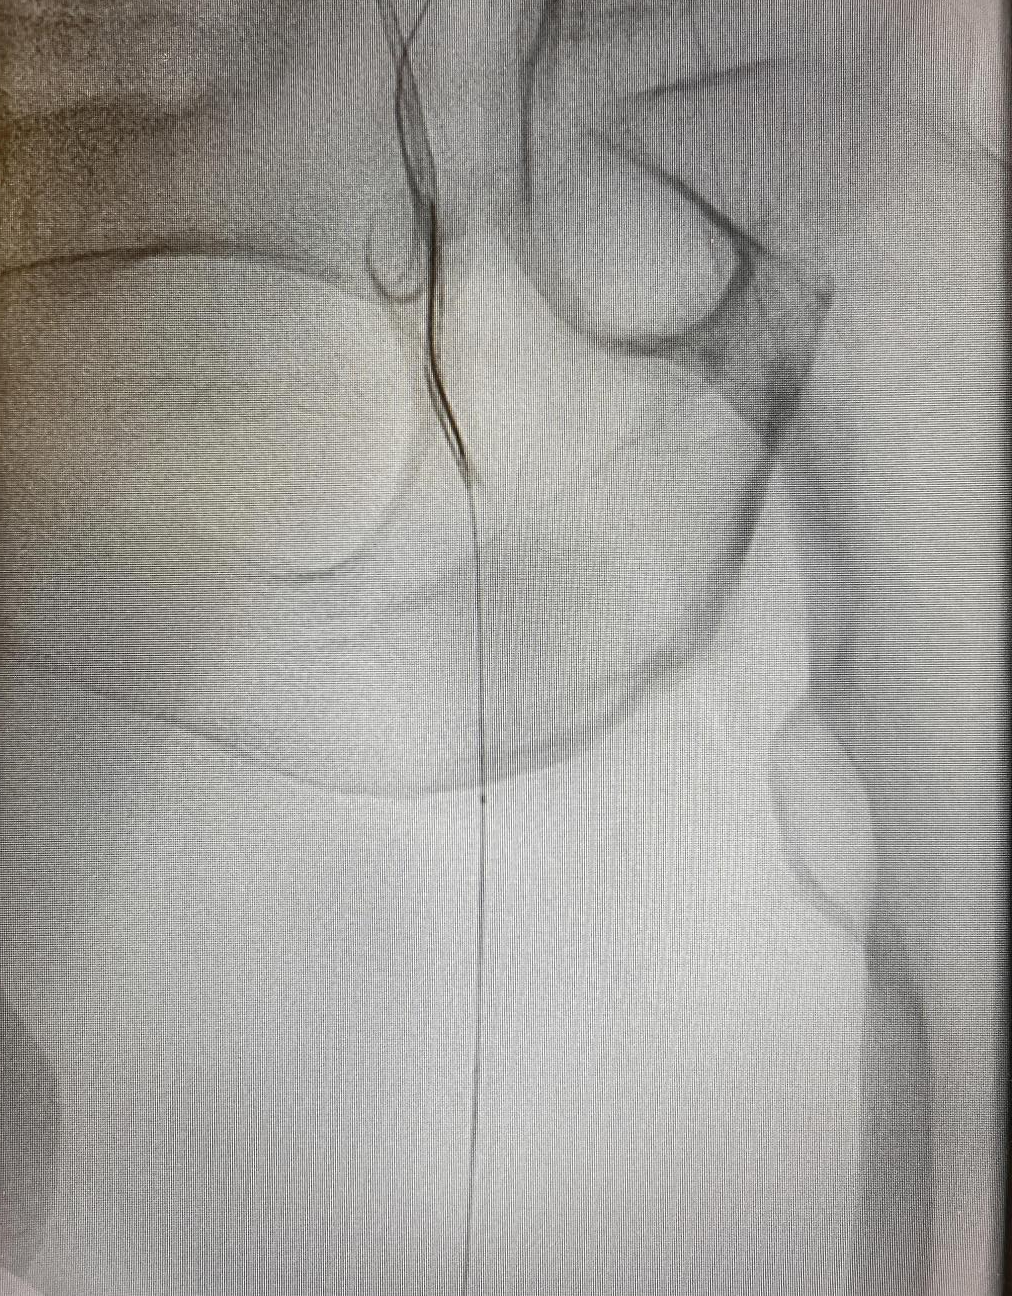

图1:下肢血管增强CT提示,左侧股浅动脉闭塞